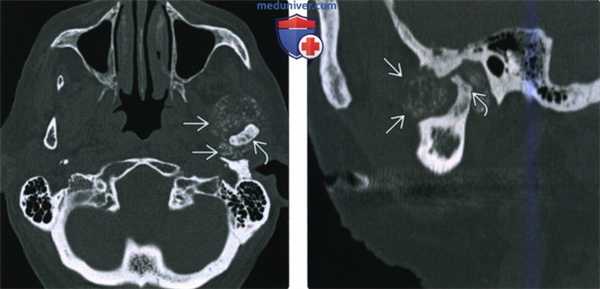

(Слева) КТ в костном окне, аксиальная проекция. Типичная хондросаркома левого височно-нижнечелюстного суаава. Мыщелок нижней челюсти склерозирован и имеет неправильную форму, внутри и вокруг сустава рассеянны множественные кальцификаты. И хотя в данном случае достаточно сложно дифференцировать заболевание от синовиального хондроматоза, в обоих случаях лечение должно быть хирургическим, а точный диагноз будет установлен после гистологического исследования.

(Справа) Реконструкция в сагиттальной плоскости, этот же пациент. Мыщелок деформирован, а часть кальцификатов находится в мягких тканях вне сустава.

(Слева) КТ с КУ, мягкотканное окно. Другой пример хондросаркомы жевательного пространства, на этот раз без кальцификатов. Образование низкой плотности окружает ветвь нижней челюаи и распространяется вокруг венечного отростка и мыщелка.

(Справа) КТ в костном окне, аксиальная проекция. Мыщелок и шейка нижней челюсти деформированы и содержат кальцификаты. Отсутствие характерных кальцификатов в мягкотканной части опухоли делает постановку диагноза затруднительной.